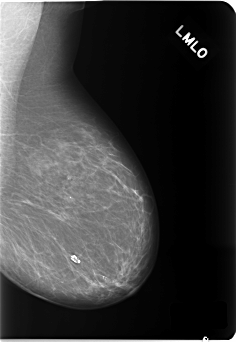

C_0140_1.LEFT_MLO

LEFT_MLO LINES 5800 PIXELS_PER_LINE 4008 BITS_PER_PIXEL 12 RESOLUTION 50 NON_OVERLAY